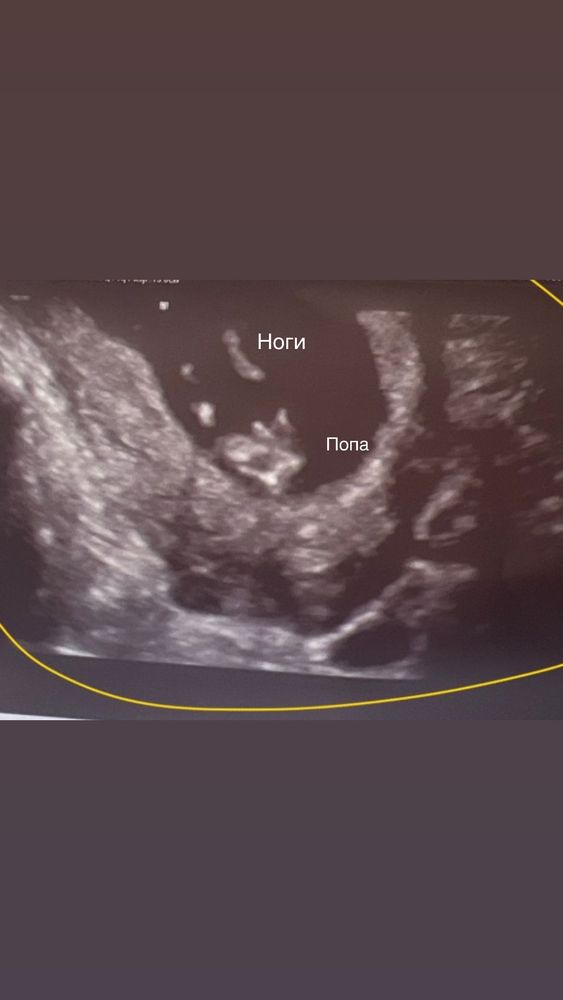

Кто на узи?

По вашему фото - либо мальчик, либо девочка.

Не вижу ничего, поставлю на девочку

По этим снимкам не буду предпологать,не видно.

Не видно даже толком как располагается половой бугорок. На этом сроке только под углом градуса можно примерно прикинуть кто будет. Если бы на втором фото видно было бы бугорок, примерно можно было предположить. Но так как не видео, можно просто по угадывать

На парня похоже)))

Мальчик

На мальчика похоже на первом фото) Но я тот ещё спец)

Со стороны попы у них одинаково на этом сроке, смотрят угол наклона бугорка в положении, как второе фото. Тут он закрыт ножкой, увы. Не видно